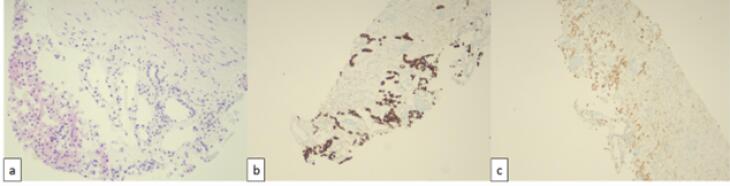

Chromophobe renal cell carcinoma (ChRCC) is a rare subtype of renal cell carcinoma (RCC). We present a case of a 61-year-old male with ChRCC who exhibited unusual metastasis to the retro-orbital area, a site rarely affected by RCC. The patient experienced diplopia and proptosis, prompting treatment with sunitinib and palliative radiotherapy. Remarkably, rapid improvement in ocular symptoms was observed following radiotherapy. Despite this localized response, the patient's overall condition deteriorated, highlighting the aggressive nature of ChRCC. This case underscores the importance of considering ChRCC in metastatic presentations and the potential efficacy of local palliative interventions.